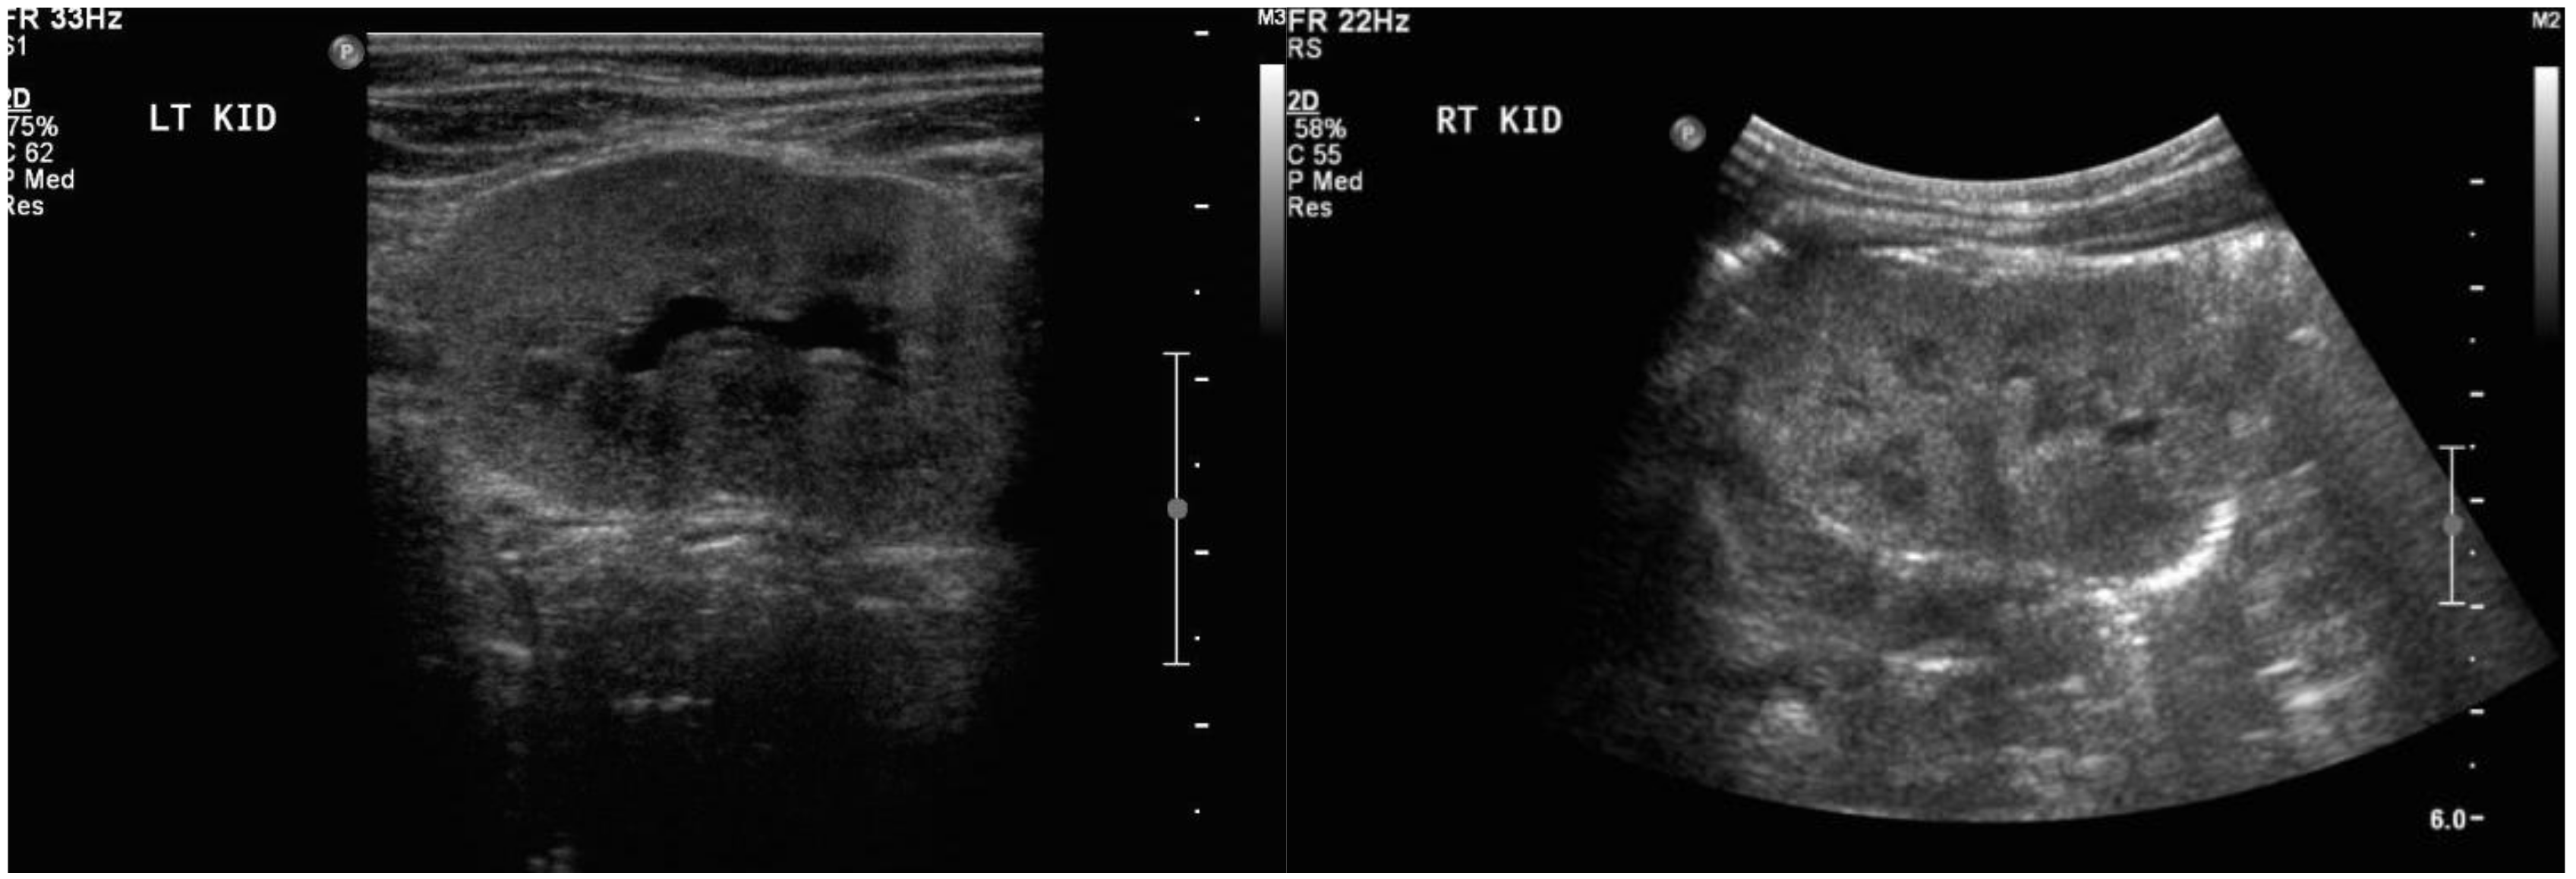

Treatment with prednisone was introduced at 29 weeks of gestation. By 30 weeks of gestation, there was trace fluid within the fetal bladder, and by 33 weeks the AFI had normalized to 15 cm. However, the fetal kidneys remained echogenic until 35 weeks of gestation, then normalized, along with a normal AFI, Doppler examination, and biophysical profile. Growth improved to the 95th centile. Spontaneous vaginal delivery occurred at 37 weeks and 2 days of gestation. The birth weight was 3.045 kg (50–90th centile) and the APGAR scores were 9 and 9 at 1 and 5 min, respectively. Initial postnatal abdominal ultrasound showed mildly enlarged kidneys with diffuse increased parenchymal echogenicity, and urine analysis was abnormal for blood and increased protein (3 g/L), with a serum creatinine of 100 μmol/L. By 6 weeks postpartum, the baby had normal laboratory values for creatinine, albumin/creatinine ratio, and protein/creatinine ratio, and the urine dipstick was negative for proteinuria and blood. Abdominal ultrasound examination performed at this time showed that both kidneys had normal structure and were of age-appropriate size, with no detected abnormalities (Figure 3). The mother’s proteinuria improved on prednisone, but did not remit. Immunosuppressive therapy postpartum included tacrolimus, mycophenolate mofetil, and plasma exchange, after which she eventually entered into remission.

Figure 3. Ultrasound images of baby’s left and right kidney at 6 weeks of age.